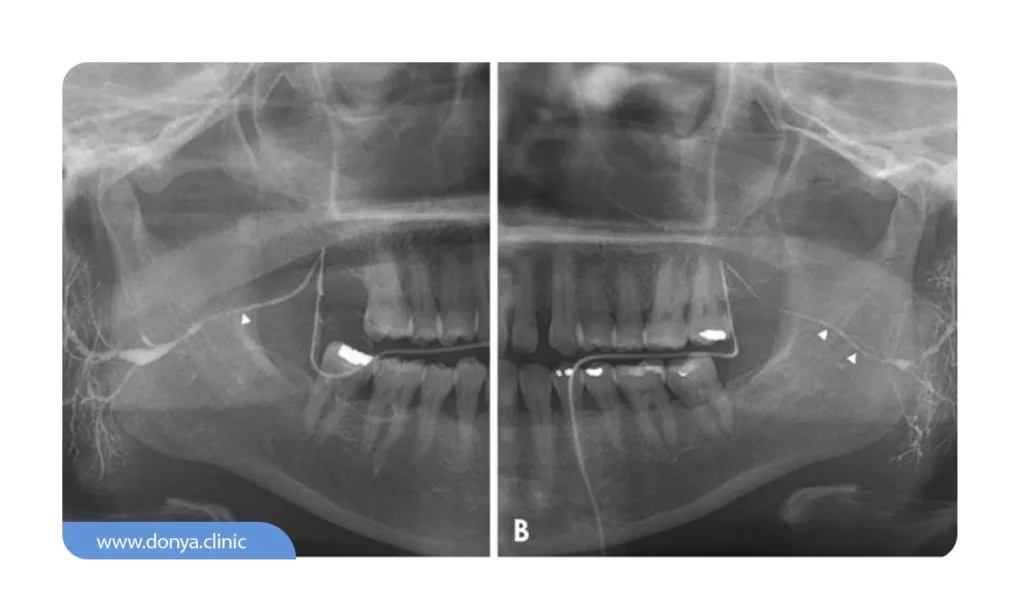

3️⃣ عکس دندان Periapical (رادیوگرافی پری اپیکال)

رادیوگرافی پری اپیکال به دندانپزشک در ارزیابی وضعیت سلامت 1 ال 2 دندان اطراف دندان دچار صدمی دیدگی کمک بسزایی می کند. در تصویربرداری پری اپیکال ارتفاع کلی ساختار متشکل یک واحد دندانی (از پایین ترین نقطه یا ریشه دندان تا بالاترین نقطه یا عاج) مشخص است.

دندانپزشکان ممکن است در وضعیت یک دندان خاص قبل از اجرای فرآیندهای درمانی نظیر استخراج آن یا پر کردن دچار تردید و شک شوند؛ محتویات و جزئیات این عکس به متخصصان کمک می کنند تا از وضعیت سلامت واحد دندانی مذکور کسب اطمینان کنند.

💵 هزینه عکس دندان پری اپیکال در سال 1404 برای تک دندان از 90 هزار تومان و برای دو دندان از 100 هزار تومان شروع می شود.

5️⃣ عکس دندان Bitewing (رادیوگرافی بایت وینگ)

هدف از انجام رادیوگرافی عکس دندان بایت وینگ ارزیابی کیفیت سلامت روکش دندانی است. دندانپزشک از زاویه 90 درجه چپ و راست چهره بیمار تصویربرداری می کند تا وضعیت واحدهای دندانی عقب و آسیاب کوچک را در فکین فوقانی و تحتانی را بررسی نماید. اگر بخواهیم به زبان خیلی ساده تر صحبت کنیم؛ دندانپزشک با استفاده از این عکس تمام جزئیات واحدهای دندانی فک بالا و پایین از یک سمت خاص دندان (قسمت تاج) ارزیابی می کند.

تصویربرداری رادیوگرافی بایت وینگ به ارزیابی کیفیت برخی از خدمات ترمیمی دندان نظیر وضعیت بریج دندان یا پر کردگی واحدهای دندانی دچار پوسیدگی کمک بسزایی می کند.